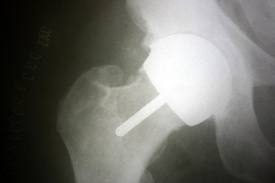

He removed the BHR and replaced it with a ceramic one THR. Though my hip is a lot better I am not pain free and on top of all of this I still experience flu like symptoms and fatigue.

I suspect from what you have told me that the first hip with its large femoral head and cup was “impinging” or rubbing on surrounding muscle and this was generating pain and eventually wear of the joint and the other symptoms. The squeaking suggests that the joint was not being lubricated by synovial fluid as would be expected – and the dry rubbing of the joint could likely have produced greater wear and the metal ion poisoning.